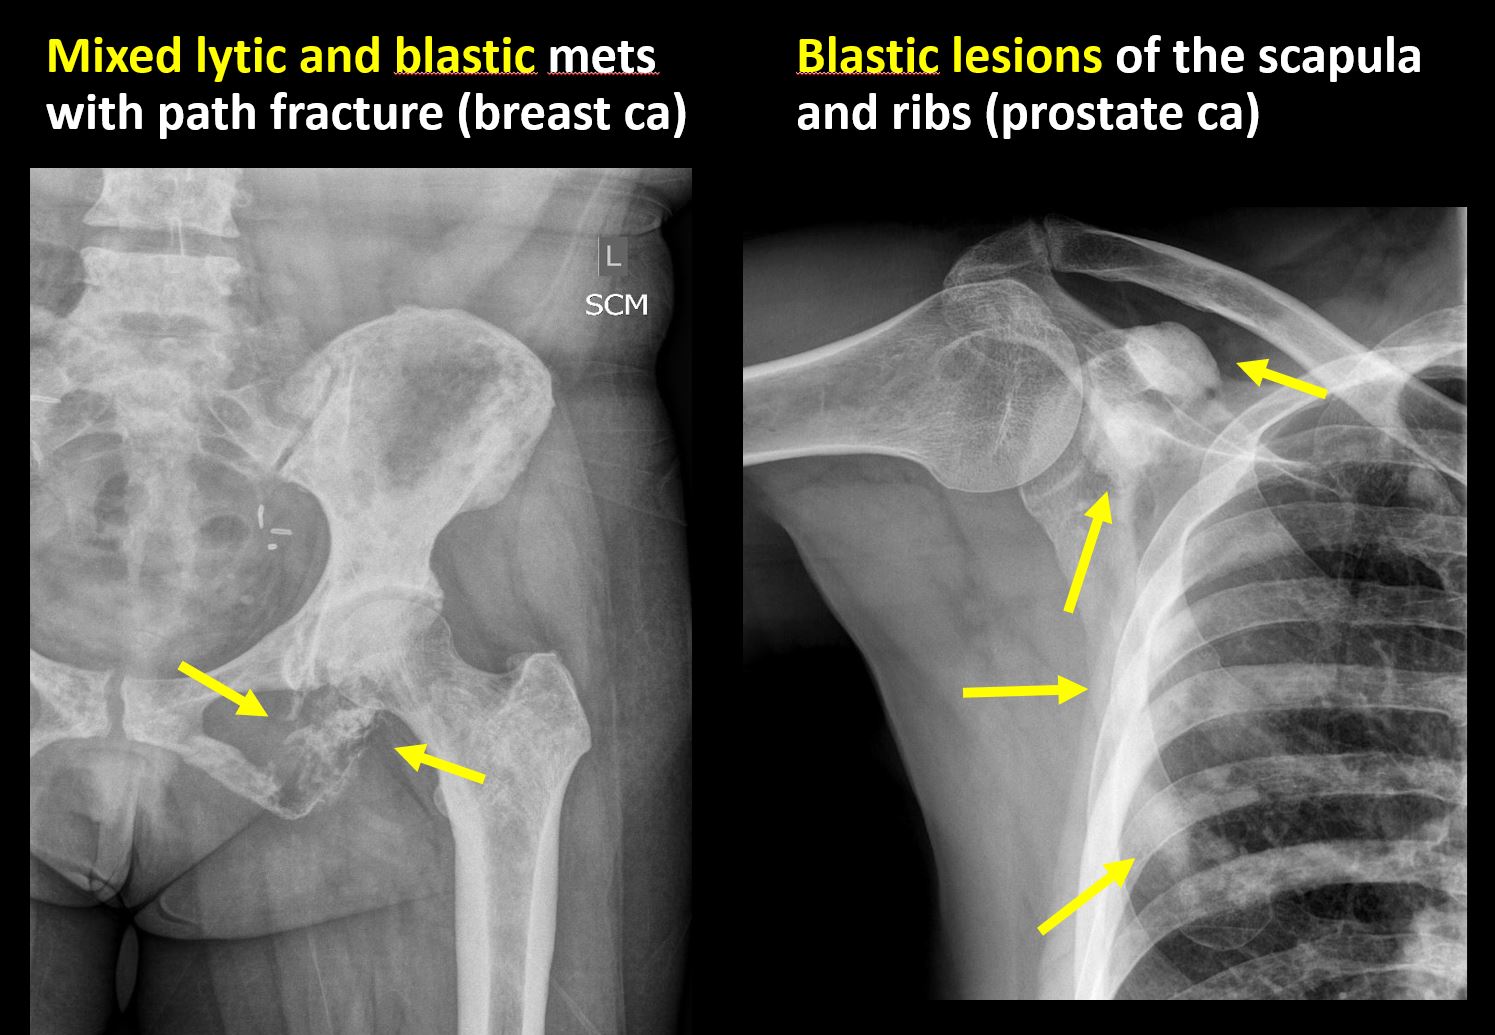

There is/are focal or multifocal lytic/lucent, blastic/sclerotic or mixed density lesion(s) or other abnormality. |

No | NA |